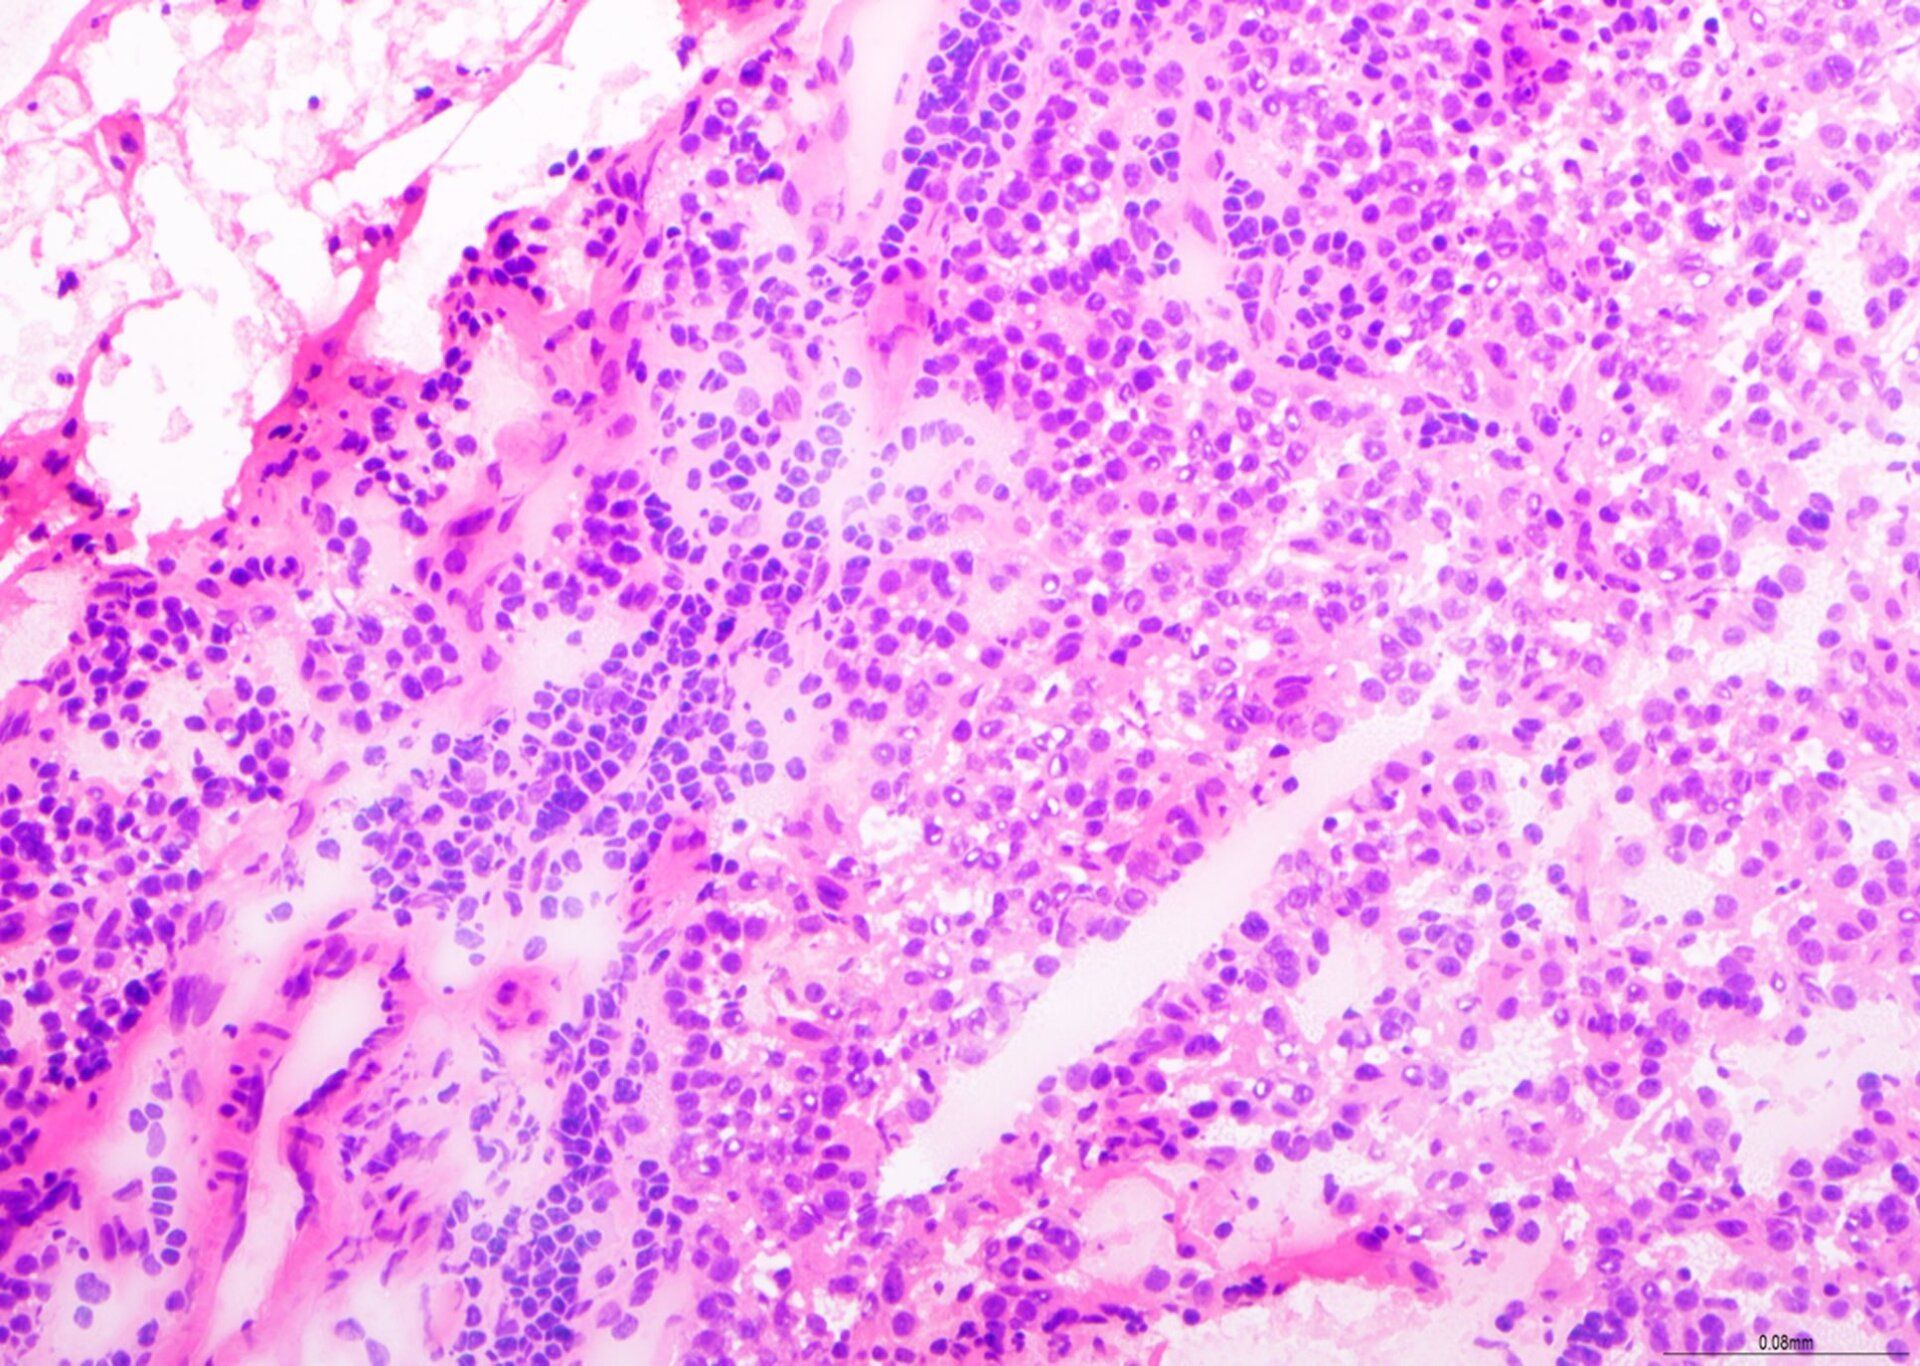

H E - BMT Scheme

Nakita sa x20. Sa pangkalahatan, napakahusay na paghahanda, ngunit ibinawas ang mga marka para sa mga fold at creases, pagkawala ng materyal, at paglamlam sa background ng haematoxylin. Ang slide na ito ay nakakuha ng 8/10.